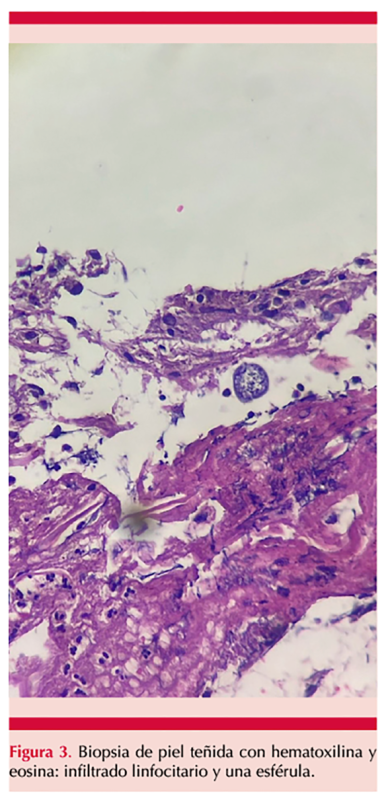

El cultivo para hongos mostró crecimiento de hongos filamentosos con colonias blancas, con crecimiento micelial algodonoso y flocoso (Figura 2). La tinción con azul de lactofenol reveló hifas que formaban artroconidios intercalados con células disyuntoras. La biopsia de piel evidenció un proceso inflamatorio crónico agudizado abscedado que penetraba la epidermis (Figura 3). En la tinción de Gomori-Grocott se observaron esférulas con endosporas en su interior (Figura 4), compatibles con Coccidioides spp. La secuenciación de ADN confirmó Coccidioides posadasii como agente etiológico, ITS: OP740677, D1/D2: OP740678. Se descartó enfermedad pulmonar, así como diseminación de ésta, y se estableció el diagnóstico de coccidioidomicosis cutánea primaria.

La microscopia directa con tinción de Gomori-Grocott, de ácido periódico de Schiff (PAS) o de hematoxilina-eosina, permite mejorar la visualización de las esférulas de doble pared retráctil, de 10 a 80 µm, con endosporas en su interior características de este hongo.7,8